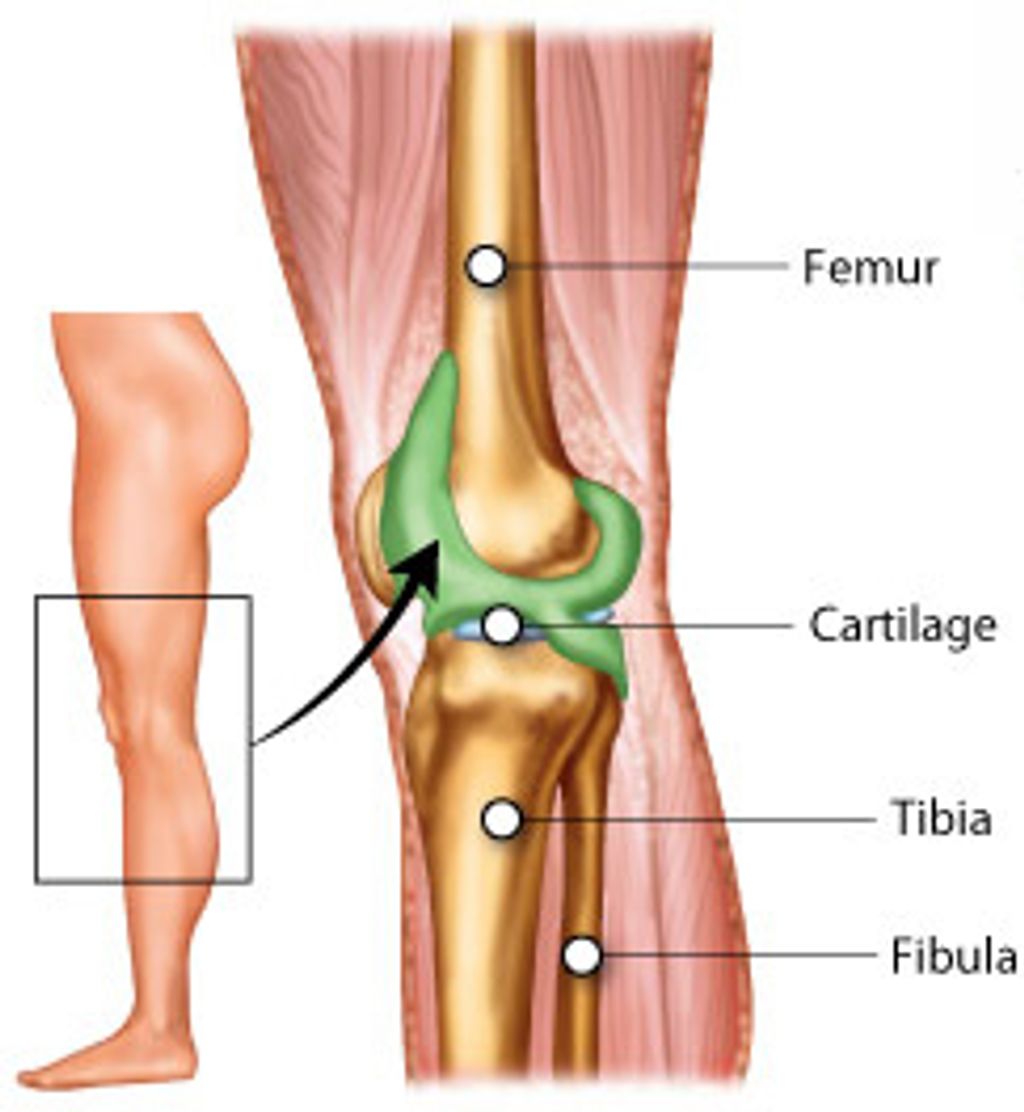

Anatomy of the Knee Joint

The knee joint is a complex structure that plays a crucial role in supporting our body weight and facilitating movement. Understanding the anatomy of the knee joint is essential for comprehending the mechanisms that can lead to anterior knee pain. The knee joint consists of the femur, tibia, and patella, all of which are connected by ligaments and surrounded by protective cartilage. This intricate arrangement allows for smooth and controlled movement, but it also makes the knee susceptible to various forms of stress and injury.

In some cases, anterior knee pain may be associated with specific anatomical abnormalities, such as patellar malalignment or abnormal tracking. These issues can lead to increased pressure on the patellofemoral joint, resulting in discomfort and reduced function. Understanding these structural variations is crucial for accurate diagnosis and effective treatment.

A key aspect of the knee joint’s anatomy is the distribution of forces during weight-bearing activities. Research has shown that the patellofemoral joint experiences significant pressure during activities like running, jumping, and squatting. This underscores the importance of proper biomechanics and muscle balance in preventing and managing anterior knee pain.

It is important to note that individual variations in knee joint anatomy can influence the development of anterior knee pain. Factors such as patellar shape, alignment, and muscle strength can significantly impact the distribution of forces within the knee joint, potentially contributing to pain and dysfunction.